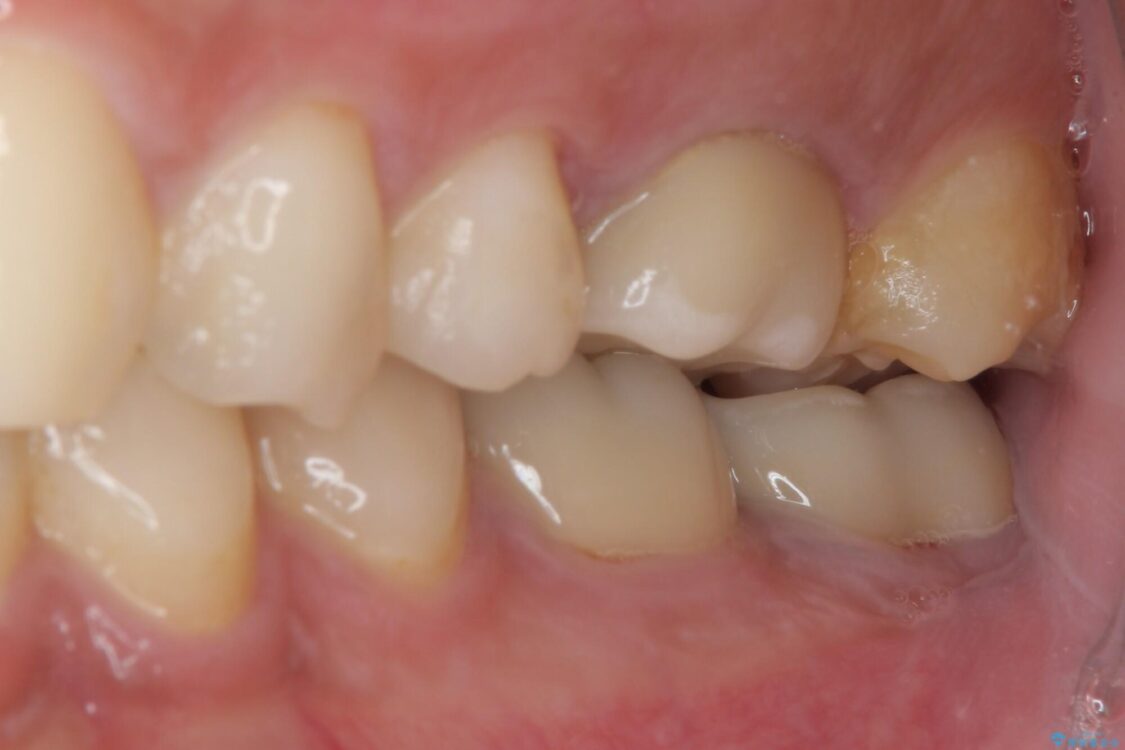

間もなく海外赴任という状況で奥歯のクラウンが割れてしまったとのことで来院された患者様です。

下顎の1番奥の歯であり、歯肉に覆われている部分が大きいためセラミックの十分な厚みが取れない状態でした。

強化セラミックを用いたオールセラミッククラウンにて補綴治療を行うこととしました。

治療前

• 海外赴任前に治したい 割れてしまった奥歯のオールセラミッククラウン 治療前画像